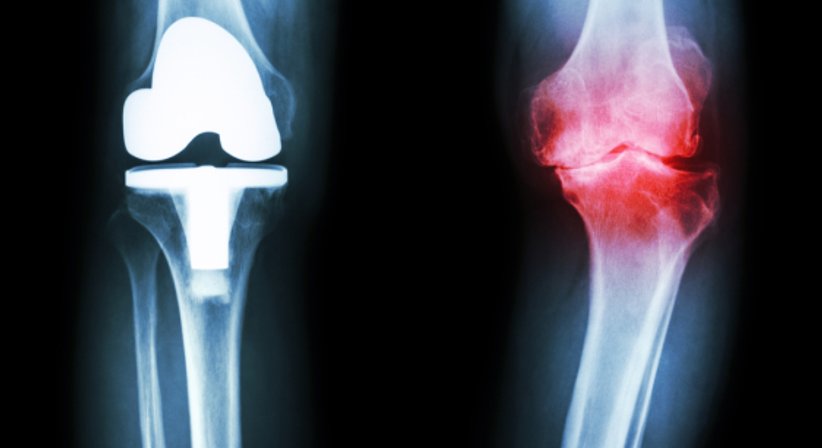

In schweren Fällen muss eine Knieprothese eingesetzt werden, um Schmerzen und Beschwerden dauerhaft zu mildern und Funktionalität sowie Belastbarkeit des Knies wieder herzustellen.

Beim implantierten Gelenksersatz handelt es sich um einen Gleitflächenersatz. Bei der Operation wird der beschädigte Knorpelüberzug durch ein Metallimplantat ersetzt. Das Aufsetzen des Metallimplantates auf den Knochen kann dabei mit dem Aufsetzen einer Zahnkrone verglichen werden. Um ein direktes Reiben der Metallstücke gegeneinander zu vermeiden, wird zwischen den Metallflächen ein Stück Polyethylen eingebracht. Zum Befestigen der Implantate wird ein spezieller Knochenzement verwendet.